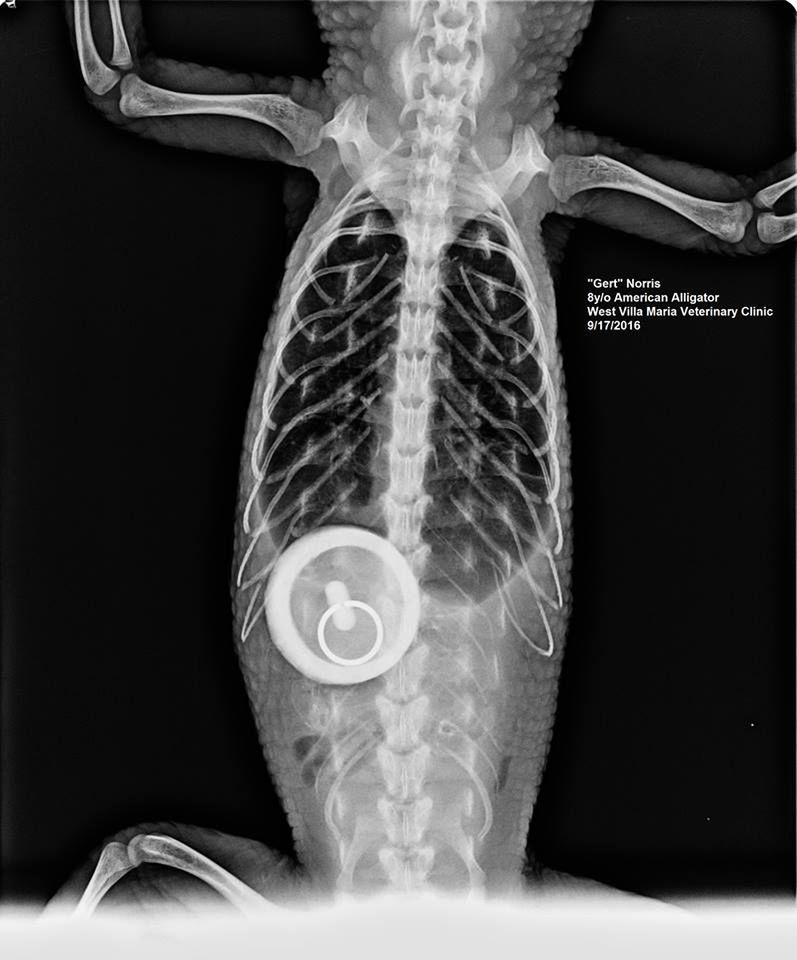

10 / 11Z wanny

Obraz

© Veterinary Practice News / James Baggs, DVM, and Kristen Norris, office manager, of West Villa Maria Vet Clinic in Bryan, Texas.

Gert, aligator mieszkający u profesora weterynarii, a służący jako żywa pomoc naukowa odpoczywał po dniu wykładów mocząc się w wannie. Lekarz uznał, że coś jest nie tak, gdy znalazł podopiecznego w wannie bez wody, a po korku nie było śladu.